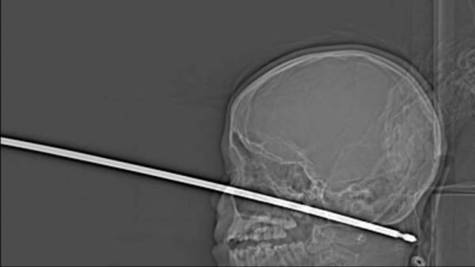

El objeto metálico le entró por la parte izquierda de la nariz y atravesó toda la cara hasta la parte posterior del cráneo.

Inmediatamente, el menor y su madre acudieron al Hospital de la Universidad de Kansas, donde los médicos calificaron el caso de “milagro”. El pincho, según ha publicado el diario ‘The Kansas City Star’, no pasó por los ojos del menor, la médula espinal ni ningún vaso sanguíneo, una de las principales razones por las que el niño sobrevivió.